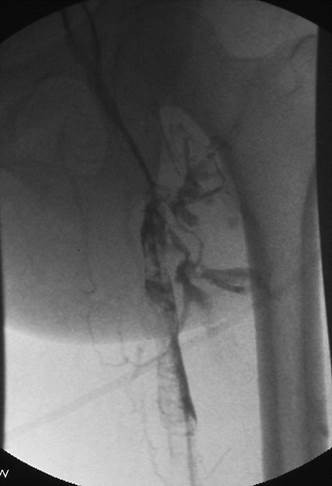

Venograma en posición de decúbito prono de la rama ilíaca izquierda que indica una estenosis causada por el tumor que comprime la uretra y la vena ilíaca externa izquierda.

Eliminación razonable del trombo en las venas ilíacas tras una sola pasada del catéter DVX de AngioJet (25 mg de tPA en 250 cc de solución salina normal).

Venograma final tras la aspiración con catéter grande y tratamiento de la estenosis subyacente (debido a la compresión extrínseca del tumor) con un stent de 16 mm con el balón inflado a 12 mm.

Tiempo total: <90 minutos. Flujo interno perfecto de la parte posterior de la rodilla a la vena cava inferior (VCI).